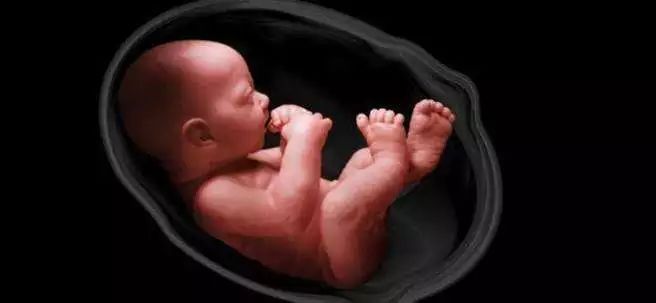

早期的羊水是由受精卵核分裂渗出的组织液形成的,中期由羊膜、胎盘、脐带渗出的组织液构成,到了怀孕5个月左右,羊水中又多了胎儿排出的尿液。

随着婴儿胚胎器官慢慢成熟,胎儿会通过不断的吞咽和排出羊水来促进自己的发育。这也就是说,妊娠中期以后胎儿排出的尿液是羊水的重要来源。所以说,胎儿其实都是喝尿长大的……哈哈~

孕妈妈平时在走路或者做其他动作时,因为胎儿是漂浮在羊水中的,所以不会被摇晃的很厉害,可以让胎儿的舒适度大大增加。

当胎儿不断长大,会经常伸伸胳膊、蹬蹬小腿,这时候羊水可以为胎儿提供充足的空间,避免空间局促而让胎儿的骨骼发育受到限制,防止胎儿肢体发育畸形。